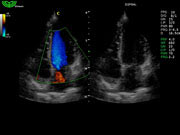

D3P64L 3.0МГц, фазированная решетка.

2.0МГц – 4.4МГц. Применения: кардиология, брюшная полость, акушерство. |

Оптимизация изображения (I-image)

- Снижает зернистость и устраняет помехи изображения.

- Улучшает гладкость изображения, при этом улучшает четкость очертаний определенных структур.